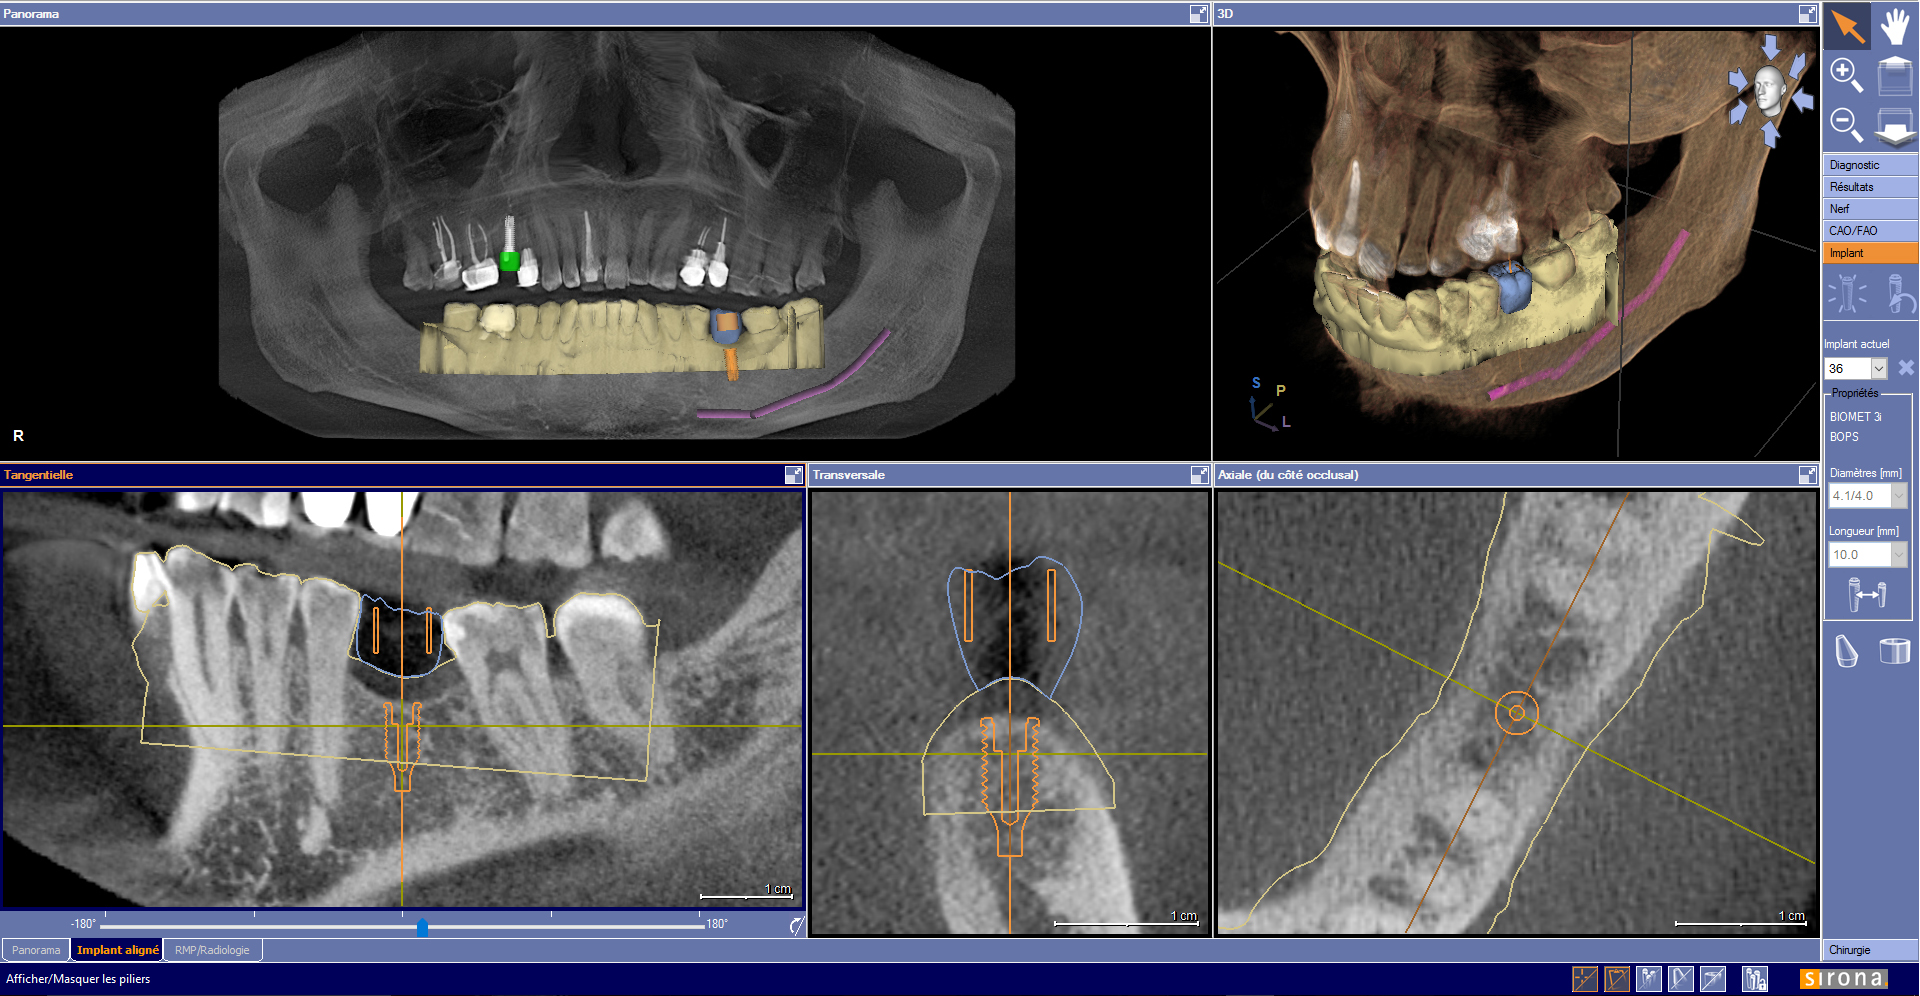

Les données de planification prothétique sont importées dans le logiciel de planification implantaire. Ainsi la position de l’implant est non seulement conditionnée par le volume osseux disponible, mais aussi par la forme et la position de la future restauration (Fig. 5).

Fig. 5 : Planification implantaire en site de 36 guidée par le wax-up numérique. Les données issues de l’empreinte optique ont été superposées aux données issues du CBCT.